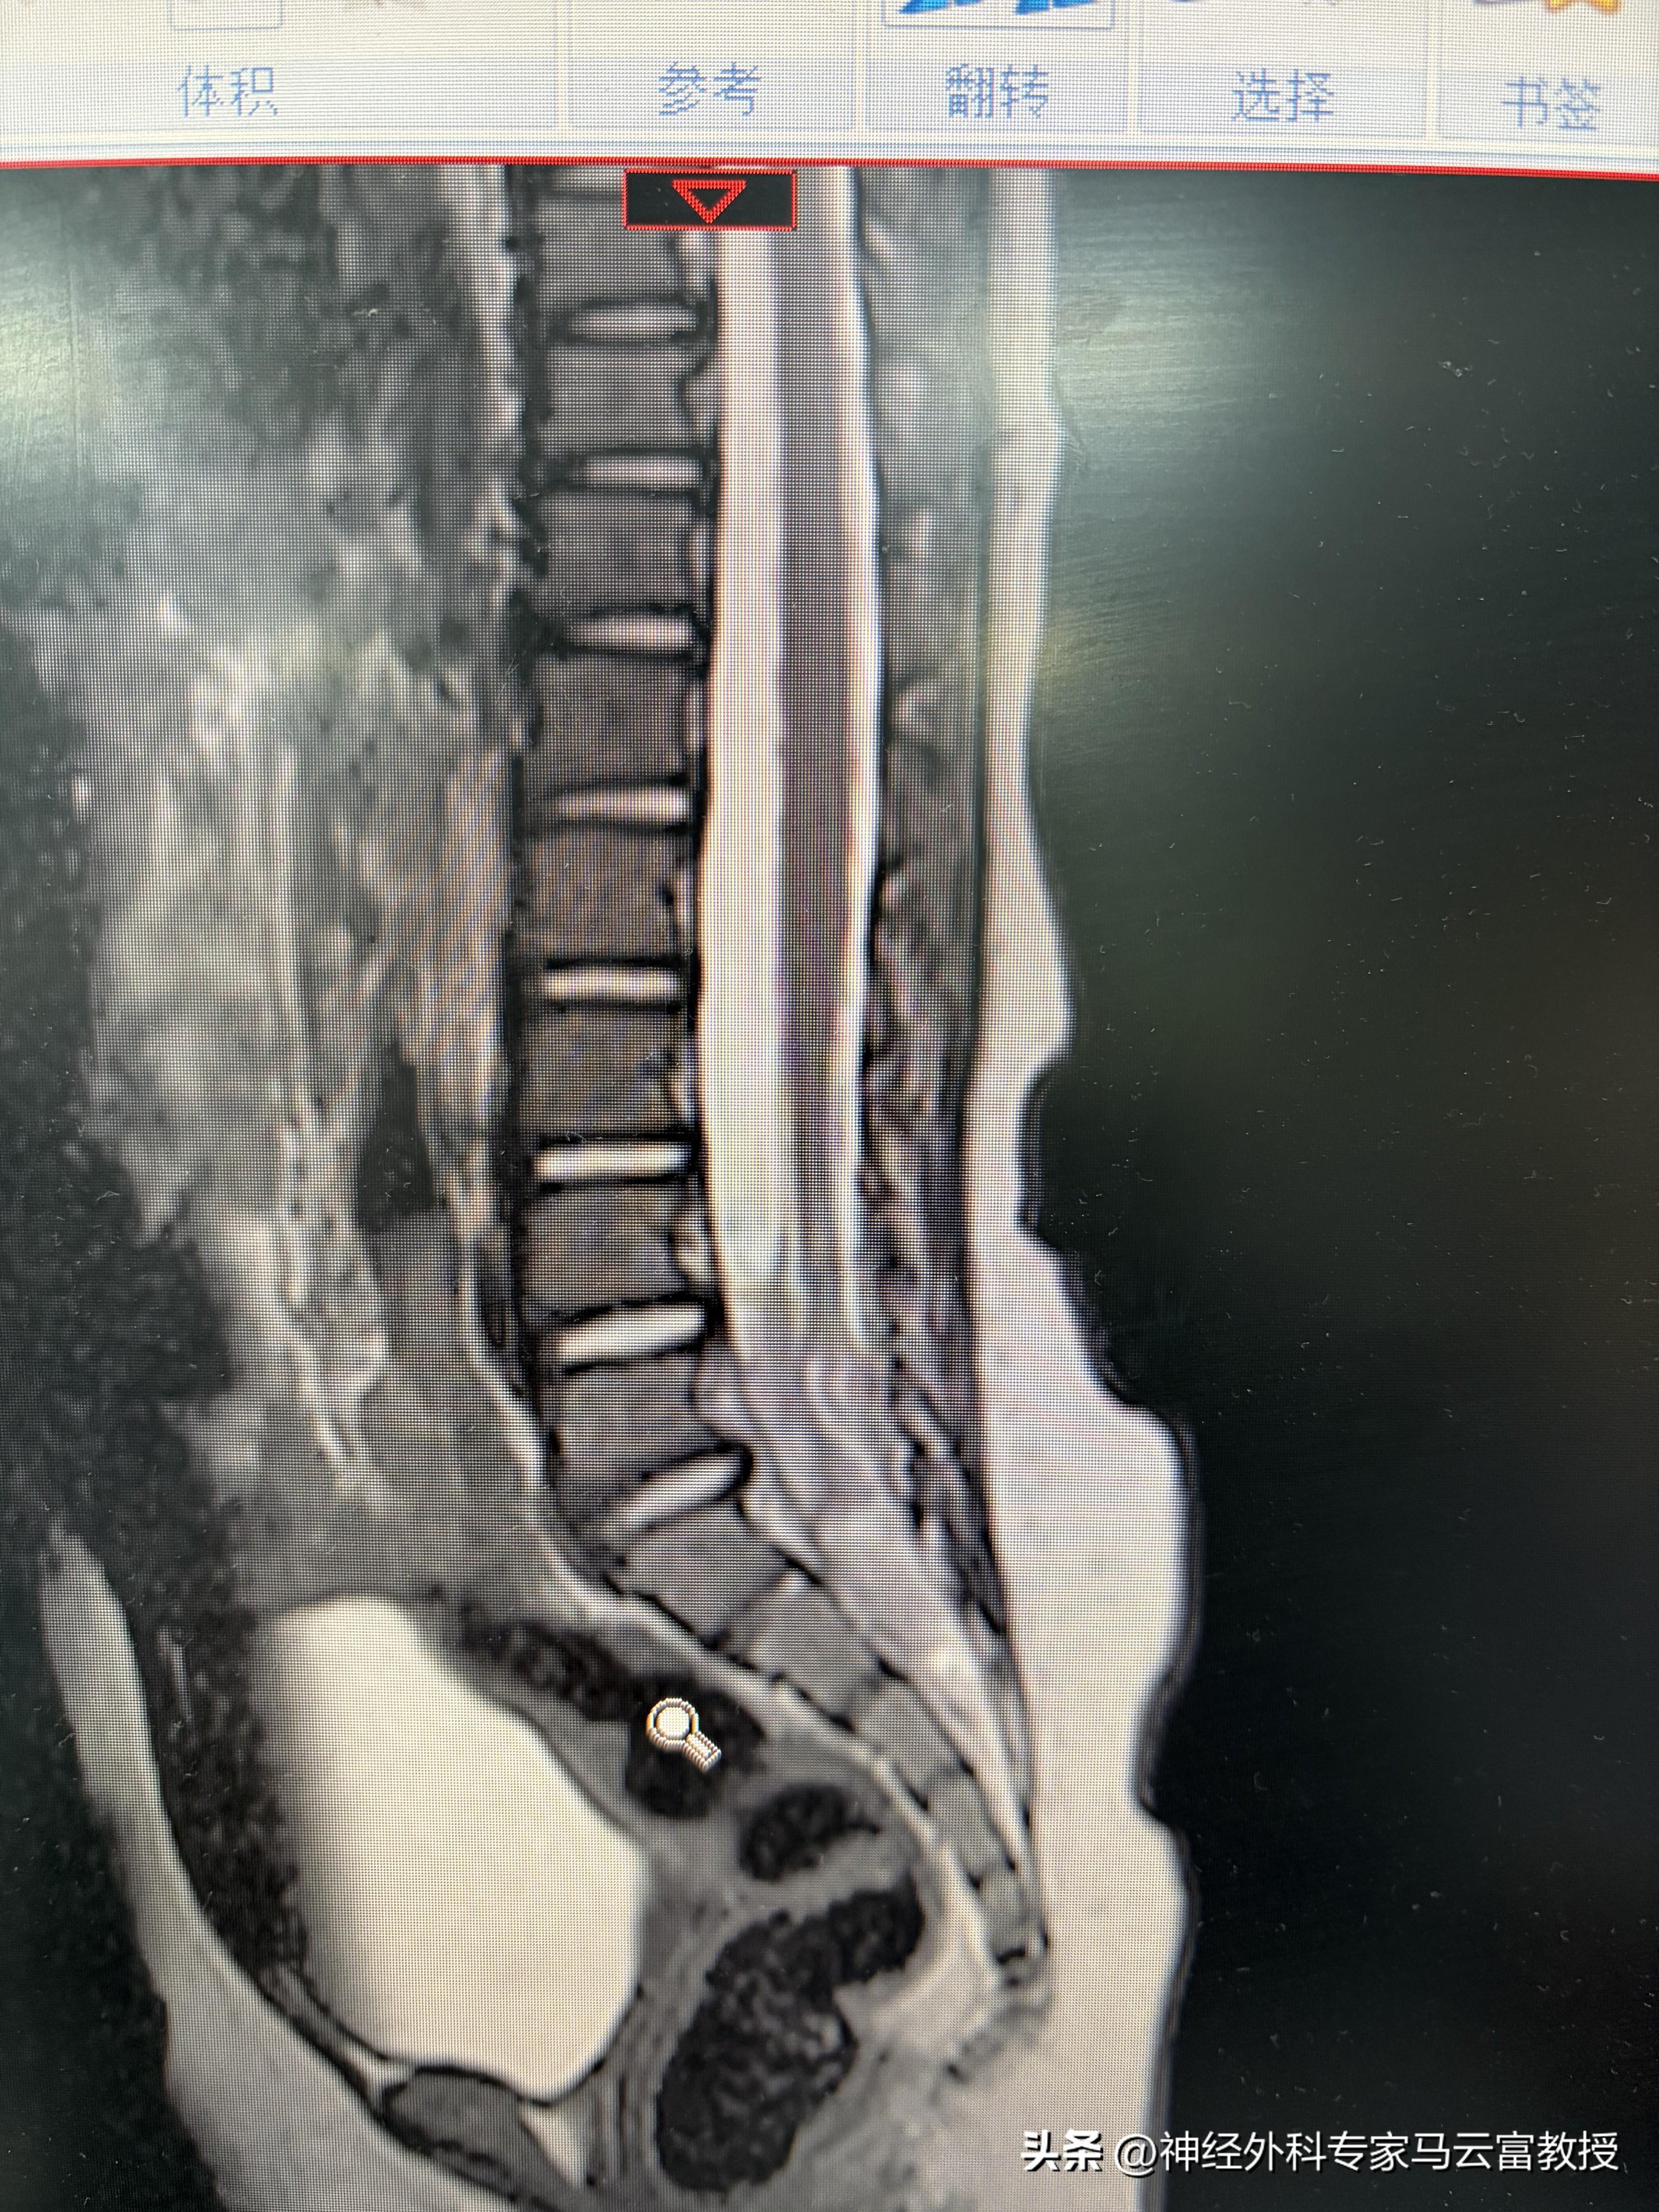

我們立刻給小禾安排了腰骶椎磁共振平掃,結果很快出來了:隱性脊柱裂,合併骶尾部皮毛竇。這個結果,既在我們的意料之中,又讓我們替孩子捏了一把汗。

脊髓圓錐低位

腰背部竇道,脊髓脊膜膨出